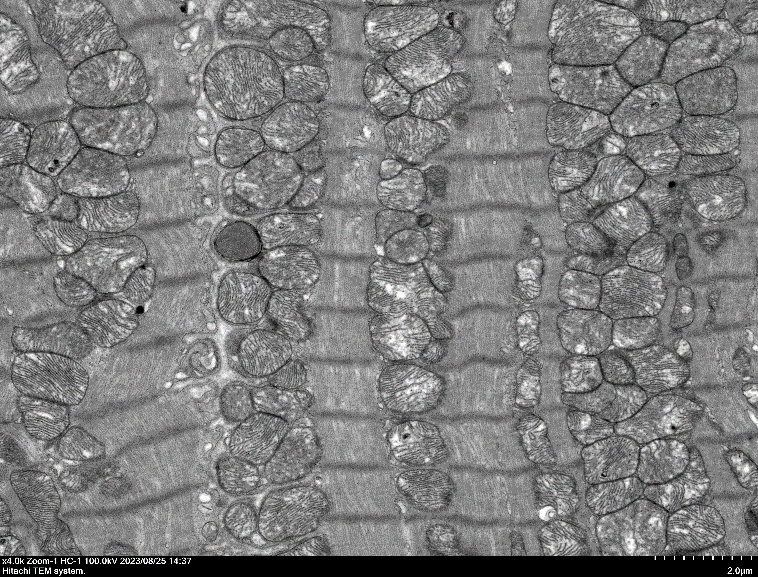

心肌超(chao)薄切片 X4000